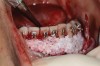

Fig 2. An abundant amount of bone biomaterial was placed during SFOT to compensate for anticipated graft shrinkage during healing.

Figure 2

Fig 3. Suturing after SFOT procedure; note the shallow vestibule post-closure.

Figure 3

Fig 4. A slight dehiscence of the flap was noted postoperatively. The prominent symphysis and associated strain of the mentalis muscle pull may have played a role in compromised soft-tissue healing.

Figure 4